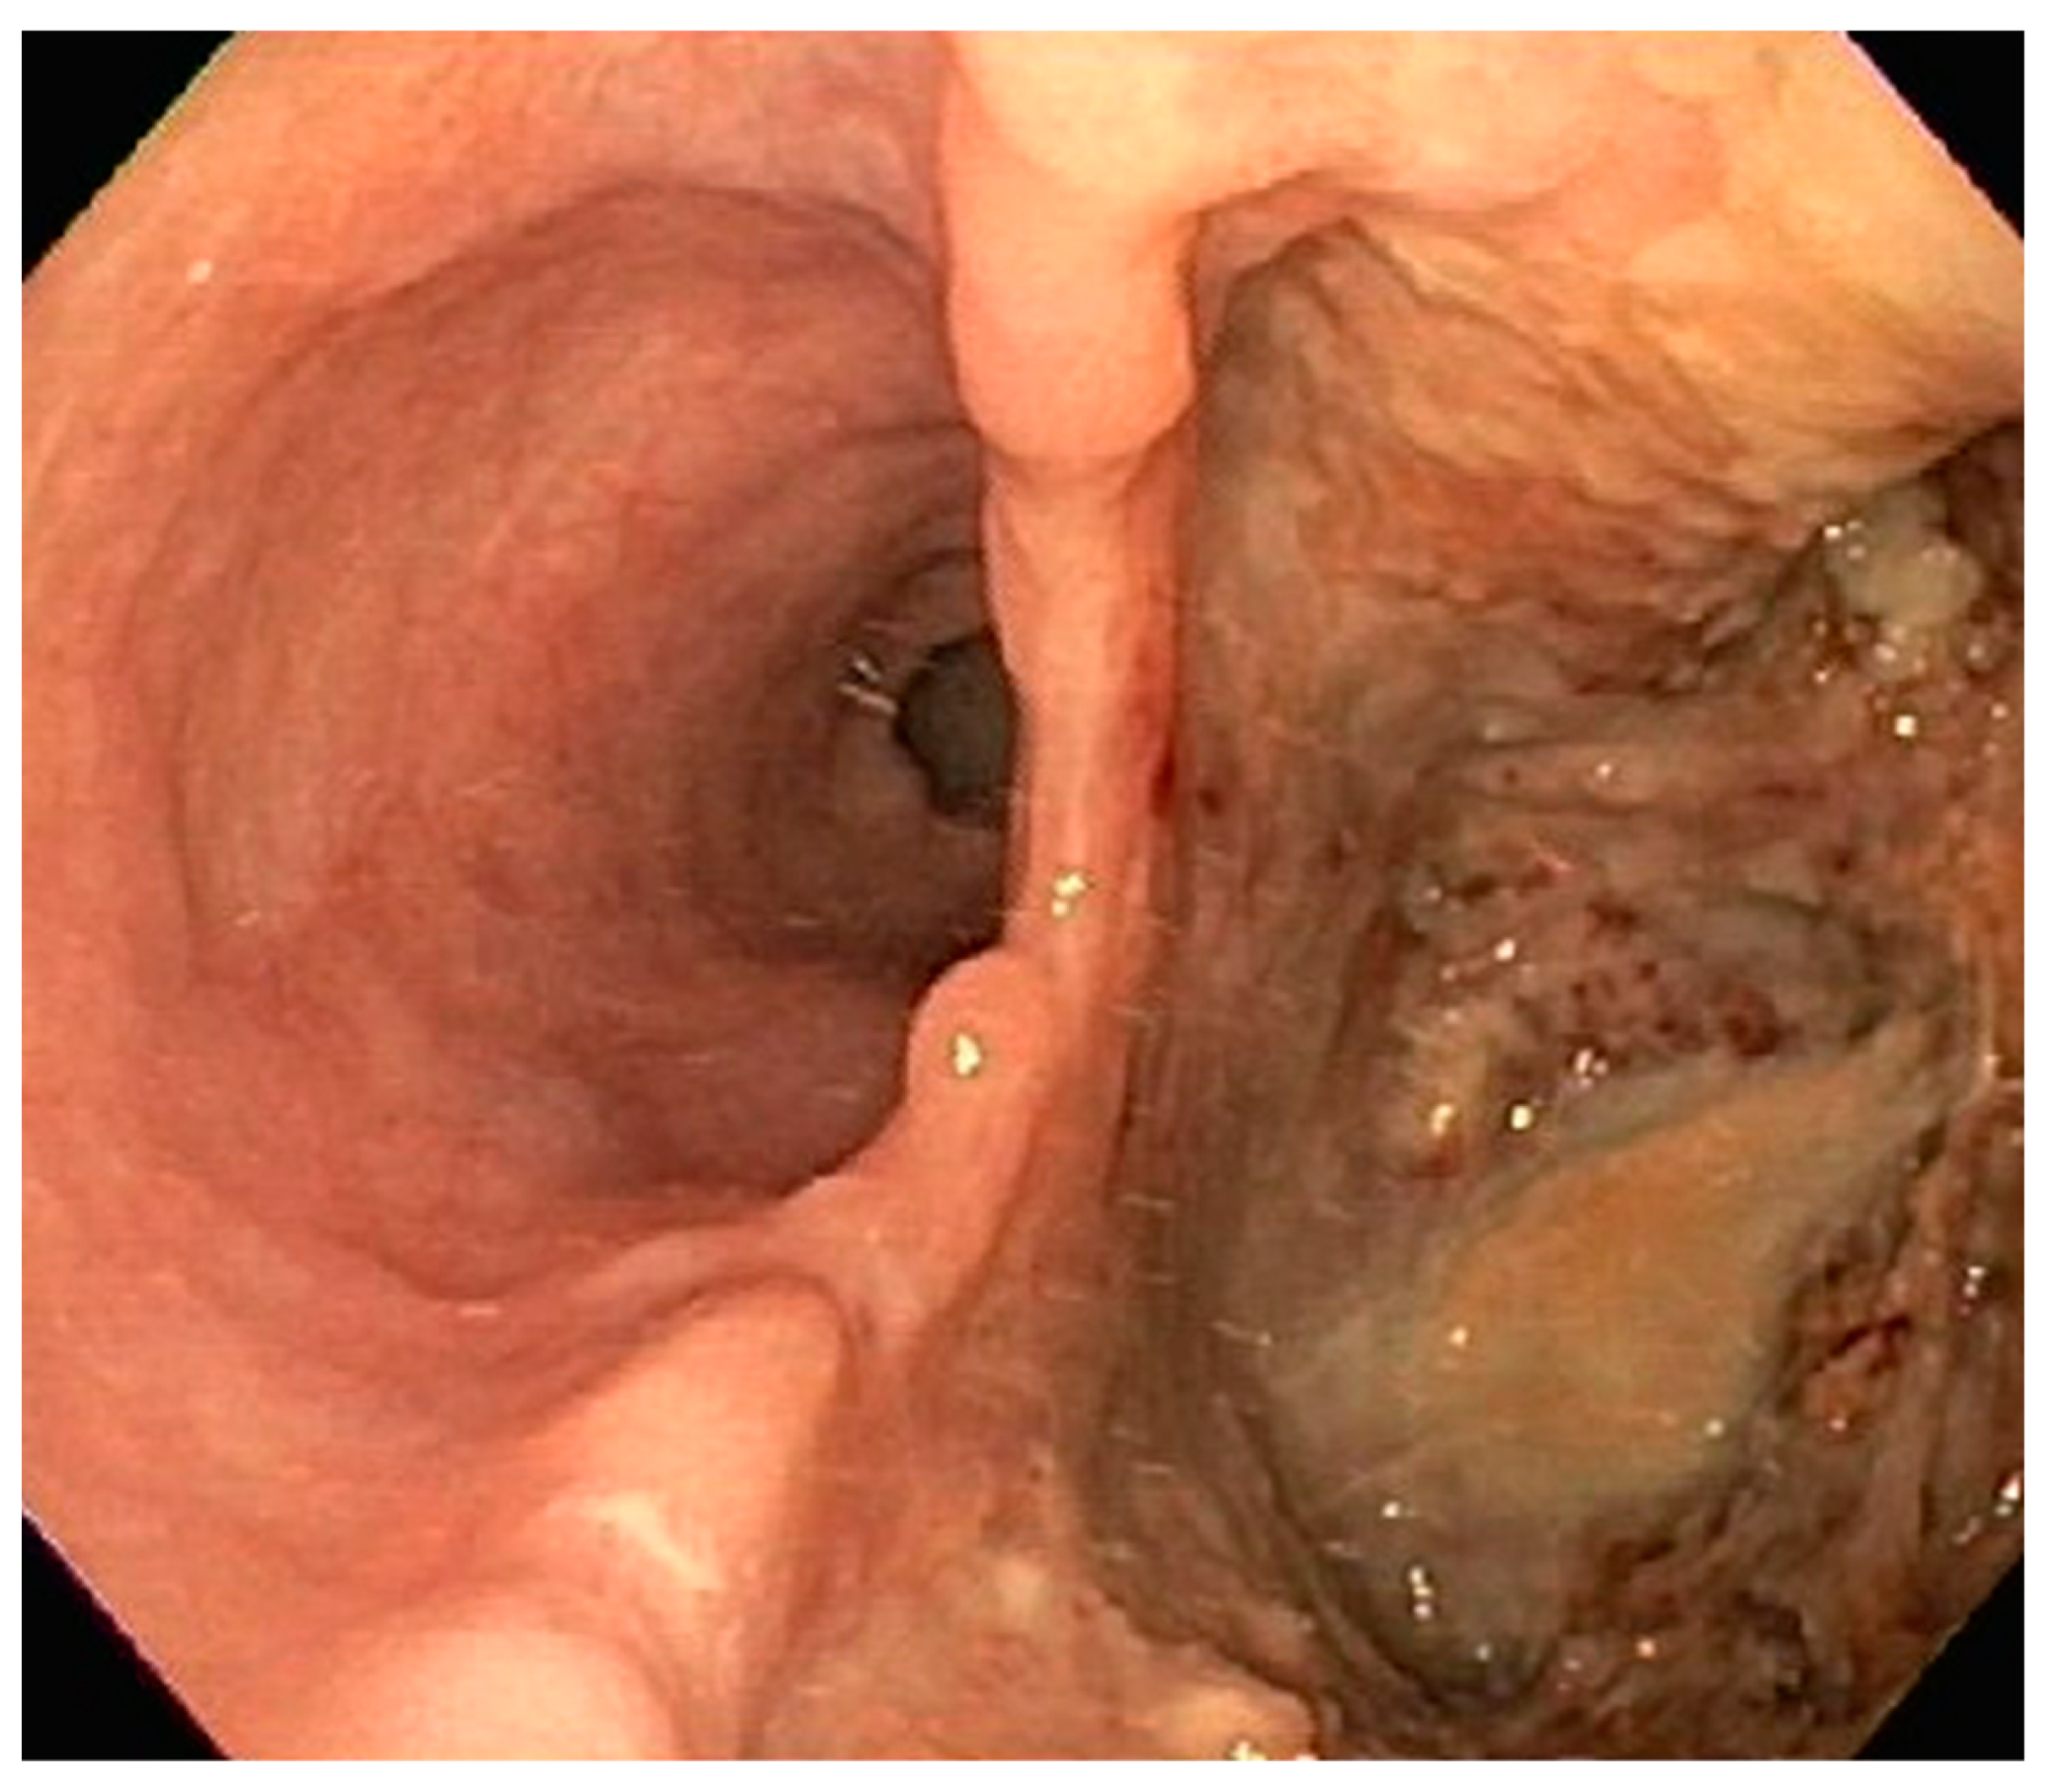

| 2 | M | 84 | Lymphoid | Fundus and cardia | Ulcerated and necrotic mass | Liver, urinary bladder | Diffuse large B-cell lymphoma | None | Death in 2 months after EGD diagnosis of metastasis |

| 5 | M | 76 | Lung | Body | Cratered ulcers | Liver, bone and adrenals | Small cell carcinoma (poorly differentiated neuroendocrine Ca) | None | Death 7 days after EGD diagnosis of metastasis |

| 6 | M | 61 | Lymphoid | Unknown | Clean based ulcer | None | Marginal zone lymphoma | Rituximab, Zanubrutinib, umbrasilib. OCHOP regimen currently | Progressive disease per latest scans despite therapy |